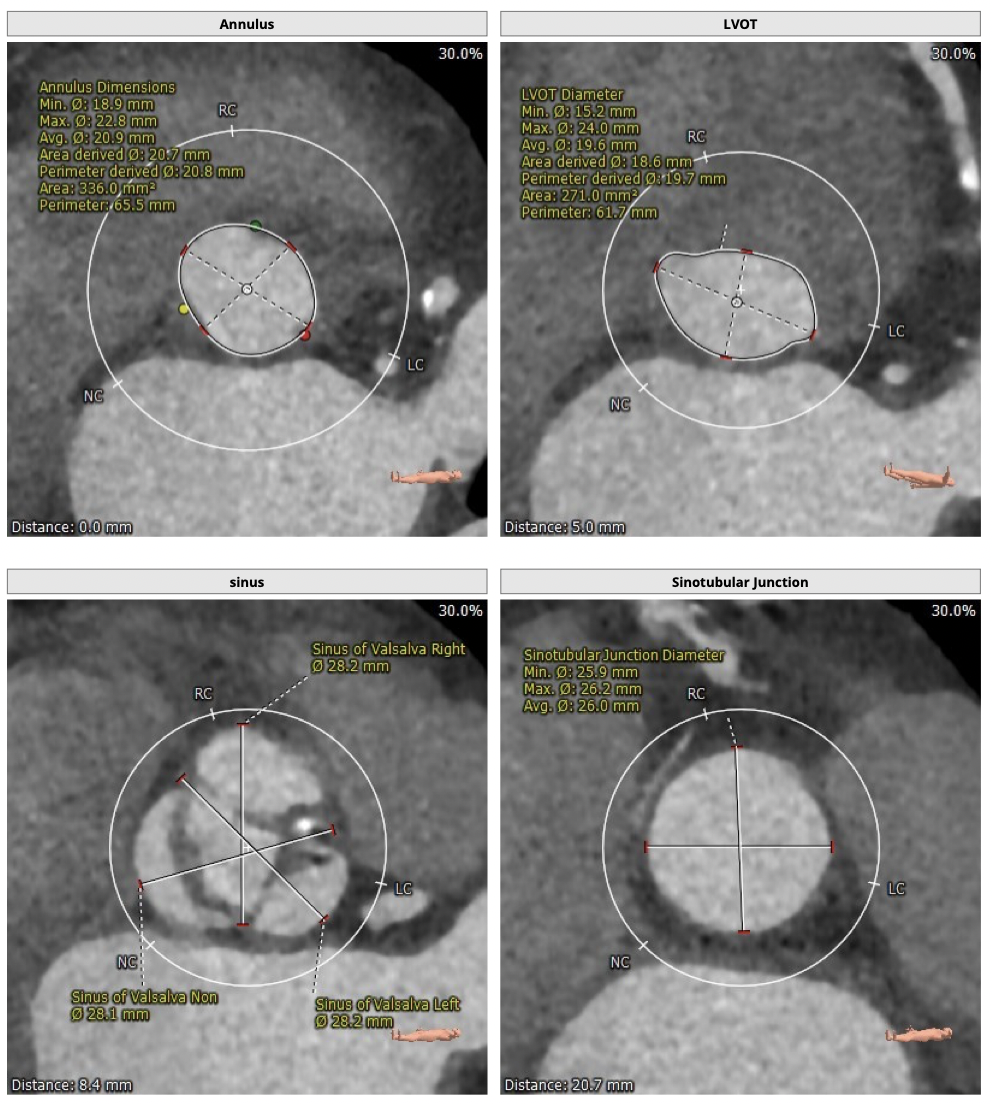

主动脉CT

难点分析:

*患者为TYPE1型二叶瓣,左右融合,重度钙化,融合脊难以推开,瓣膜释放后具有一定瓣周漏风险;

*心脏角度为57°,横位心,输送器过瓣难度增加,瓣膜植入同轴性差,瓣膜释放更易移位,增加了操作的难度;